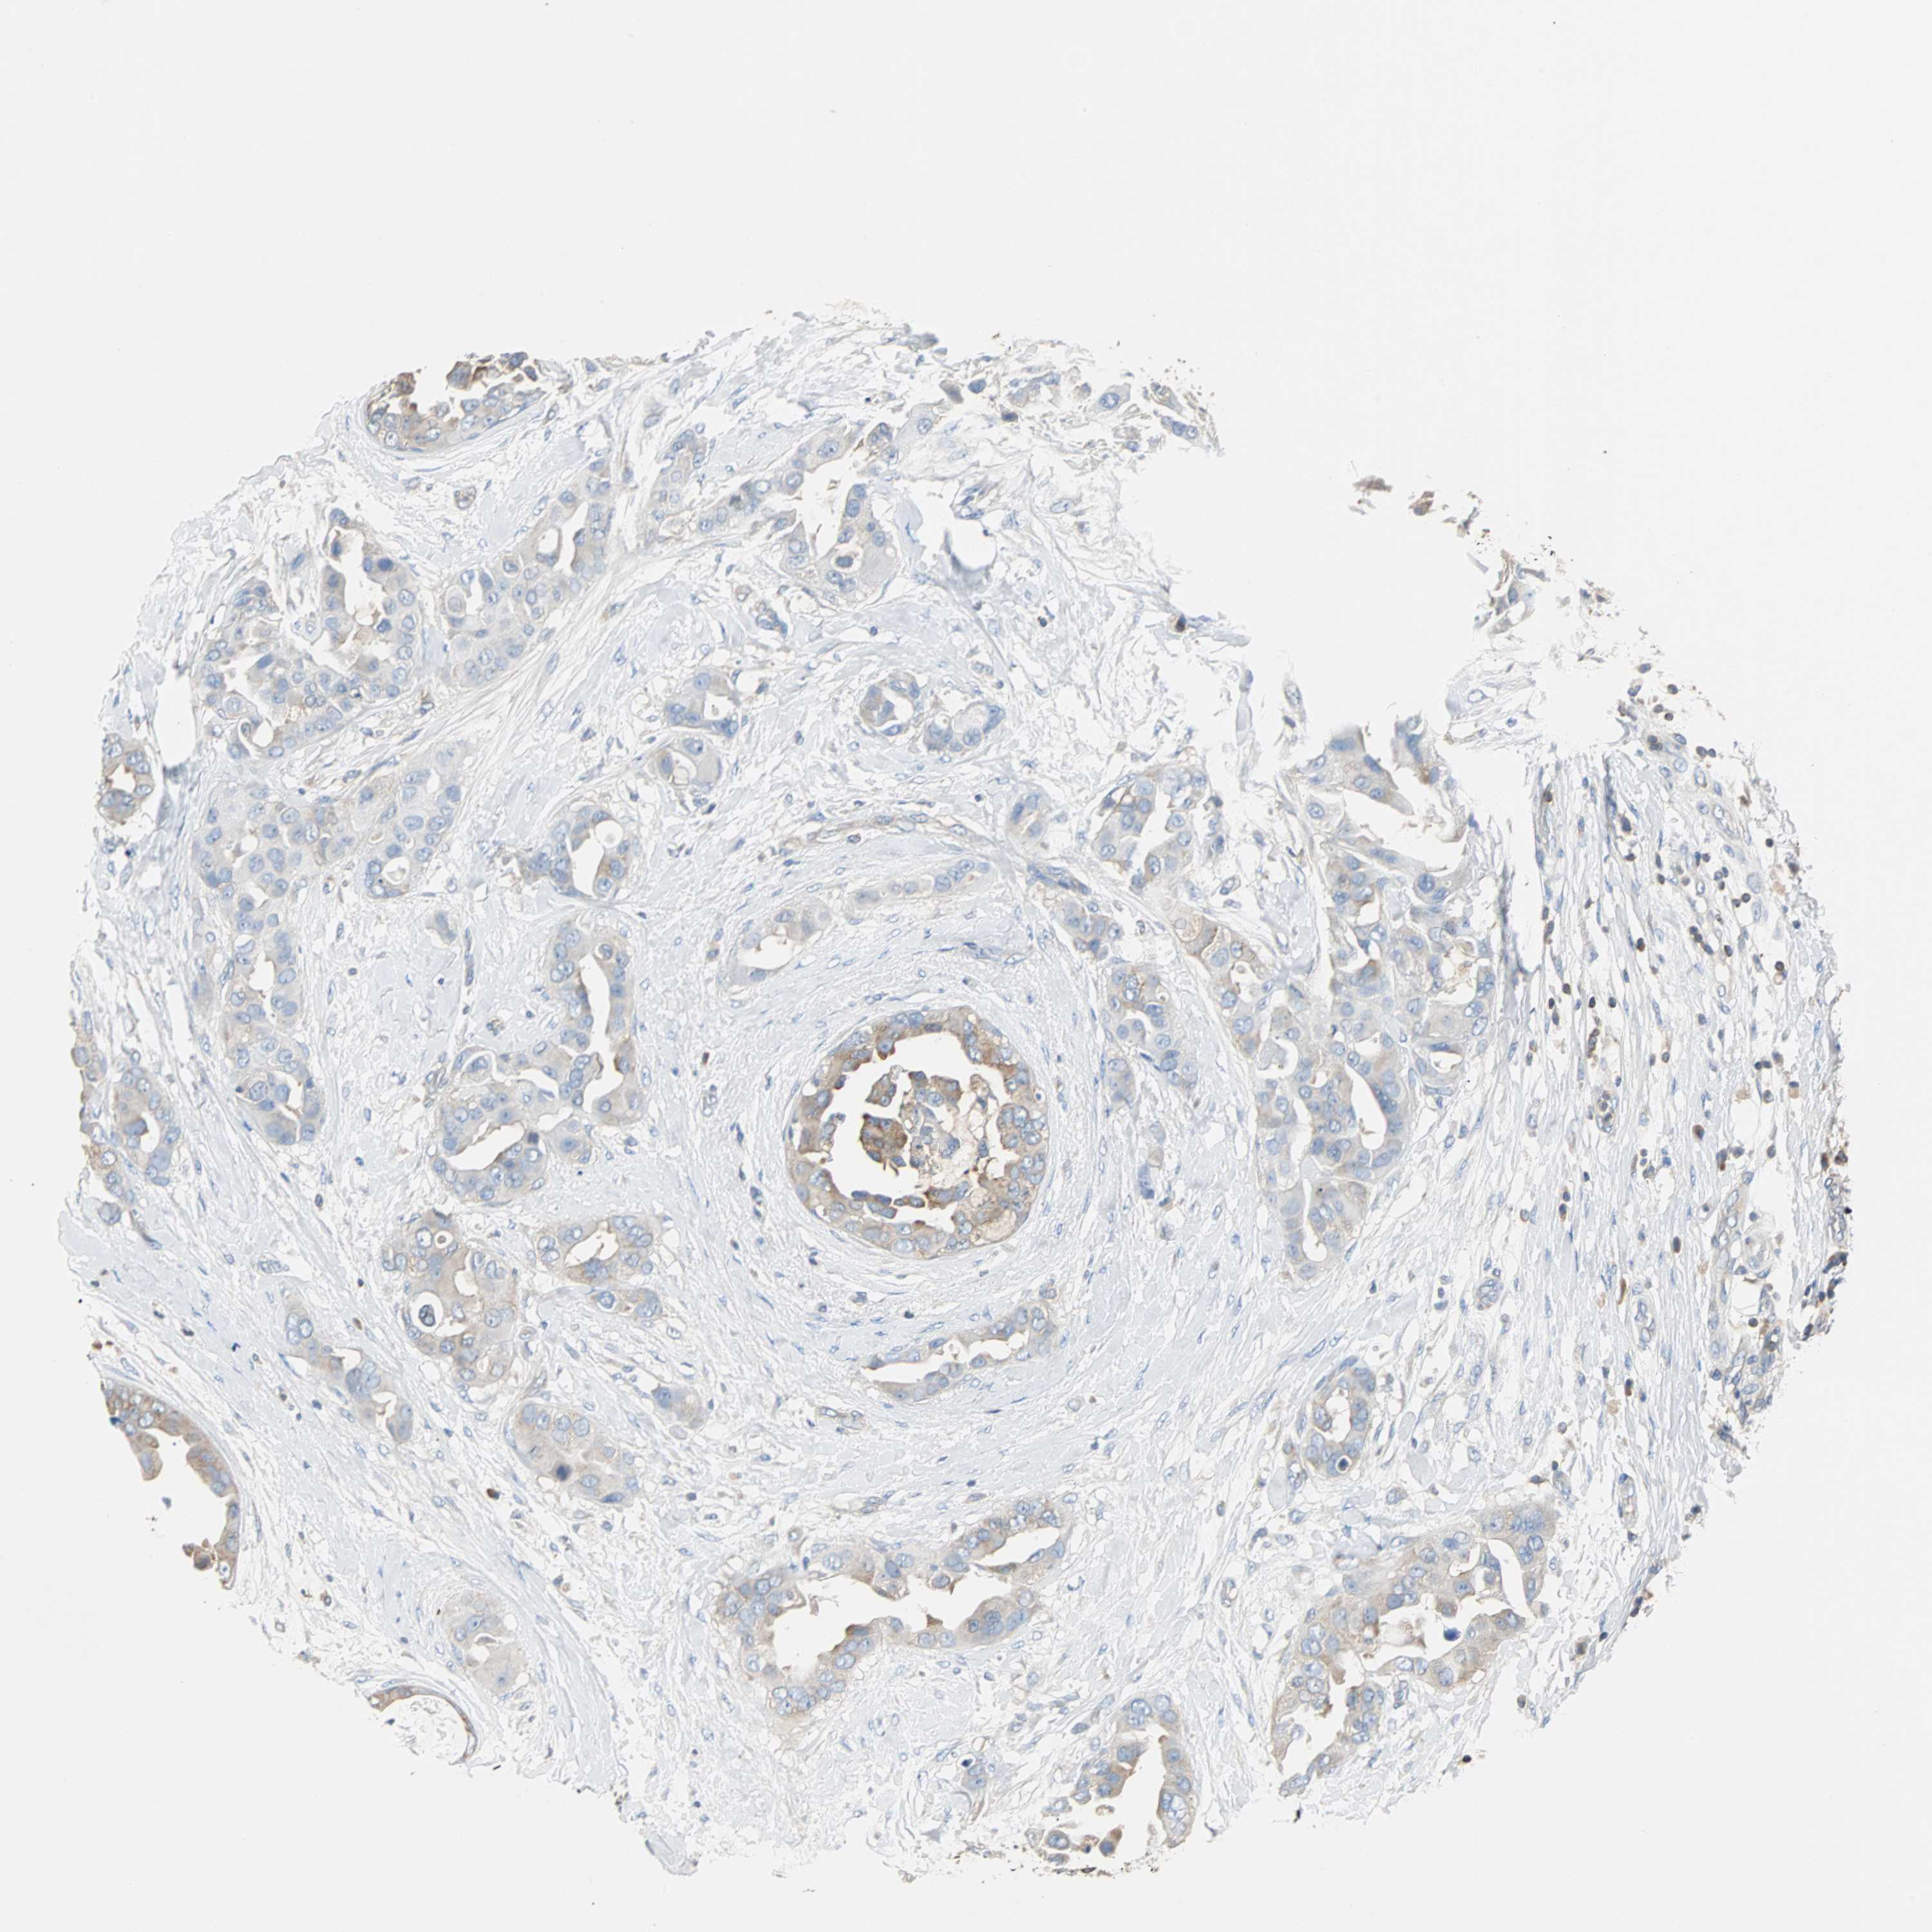

BRCA TCGA BRCA VALIDATION PROTEIN EXPRESSION